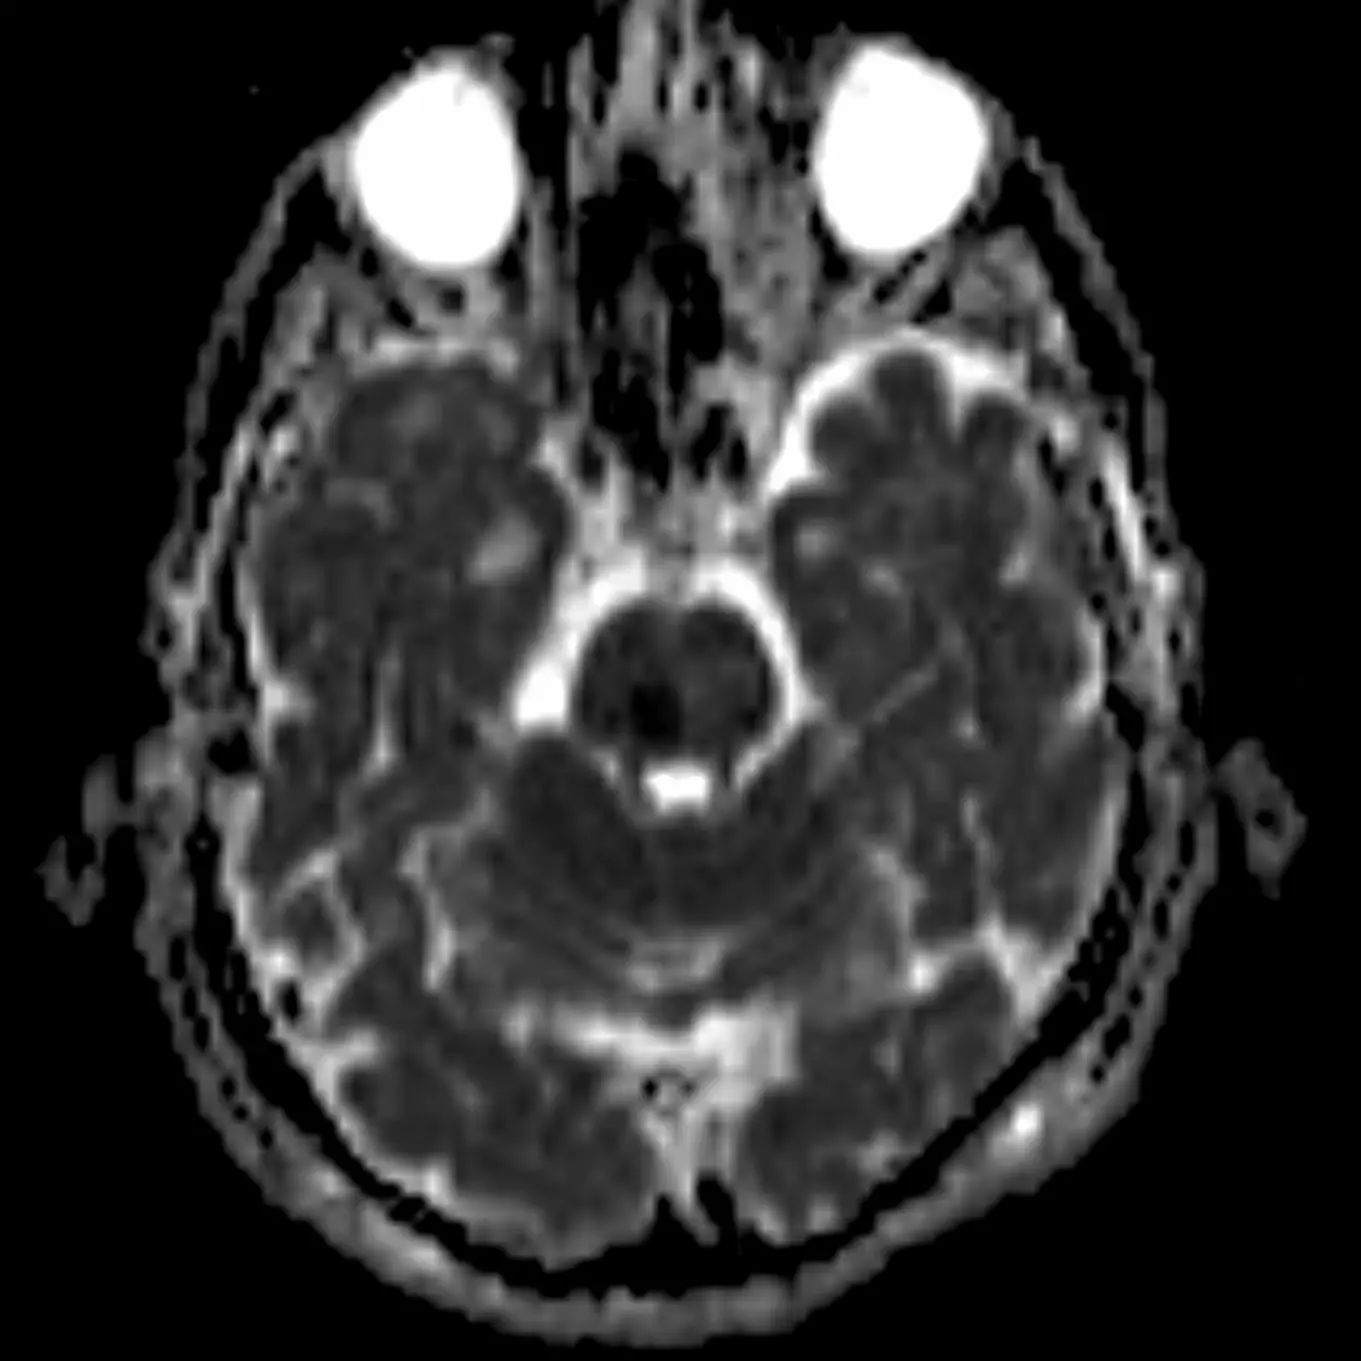

3. Decussation of the superior cerebellar peduncles

The superior cerebellar peduncles are seen in the next section, but they cross at this level in the center of the midbrain as the fibers travel superiorly.

The fibers of the superior cerebellar peduncles are highly organized causing water molecules to move along the myelin sheaths in relatively uniform directions (i.e. anisotropy). This often causes mild physiologic diffusion restriction that may be misinterpreted as an infarction. Nonetheless, infarction in this region can occur characterized by bilateral cerebellar ataxia called Wernekinck commissure syndrome, which is highly unlikely without supporting clinical history. Absence of this decussation occurs in Joubert syndrome and other ciliopathies, producing a "molar tooth" appearance of the midbrain.